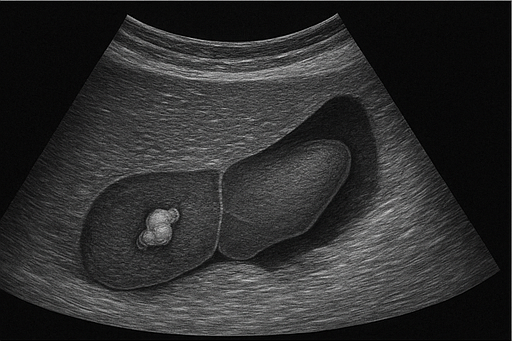

- 담석: 담낭이나 담관에 생긴 돌로, 초음파에서 밝은 음영과 그림자로 나타납니다.

- 담낭염: 담낭에 염증이 생긴 상태로, 담낭 벽이 두꺼워지고 통증이 동반될 수 있습니다.